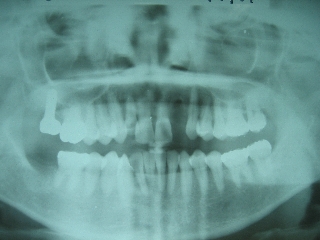

インプラント治療の為の矯正治療症例2

初診時年齢52歳。上顎前歯部欠損部インプラント治療前の咬合改善目的に来院。

当院にて前歯部の被蓋の改善を行った。

インプラント治療は専門医にて行った。